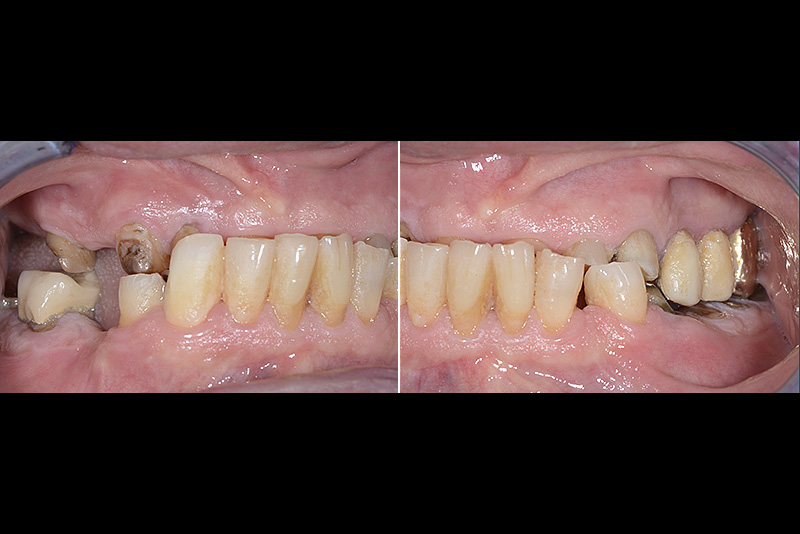

PREMESSA: in seguito all’estrazione dell’incisivo laterale superiore di destra, resasi necessaria per cause batteriche, si decide di affrontare il caso con il posizionamento di un impianto in sostituzione dell’elemento mancante dopo guarigione del sito infetto. Con tecniche rigenerative sia dei tessuti ossei mancanti a causa dell’infezione pregressa, sia dei tessuti gengivali che appaiono inizialmente troppo spostati in alto, si ripristina una corretta morfologia delle parabole (contorni) gengivali e delle papille interdentali (triangoli di gengiva tra due denti vicini).

Vengono utilizzati 2 tipi di provvisori: il primo, cementato ai denti vicini, viene utilizzato dal momento dell’estrazione del dente fino ad impianto osteointegrato (circa 6 mesi); il secondo, avvitato direttamente all’impianto, ha una funzione di prova estetica ma soprattutto di guida per la maturazione dei tessuti gengivali peri-implantari portandoli verso la maturazione completa prima di posizionare la corona finale in disilicato di litio.